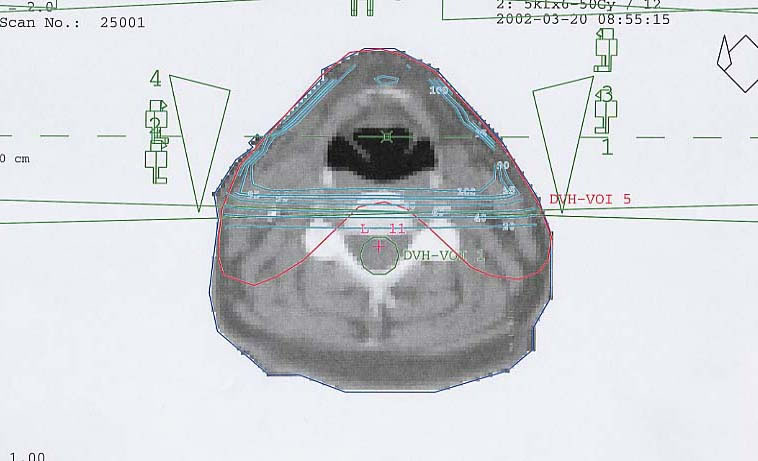

Schilddrüsenkarzinom: Bestrahlungsplan